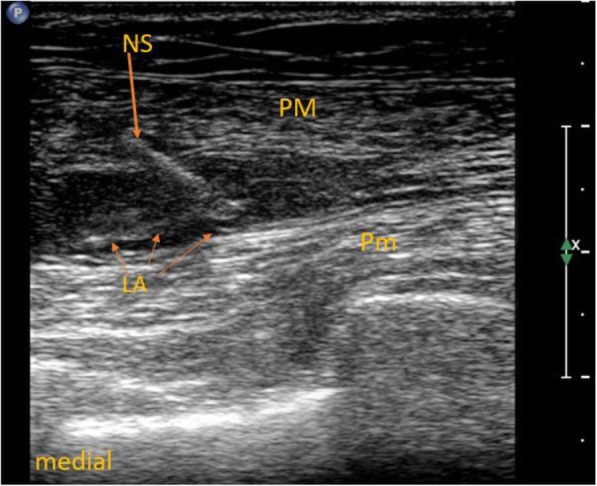

In the ESP group, ultrasound-guided ESP block at the fourth thoracic level was performed before the surgery and induction of general anesthesia with Ropivacaine (0.375%; Ropimol, Molteni, Italy, 0.2 mL/kg) as described in our previous study (Fig. 1) [13]. The maximum dosage of ropivacaine could not exceed 20 mL in this group. In the PECS + ESP group, in addition to ESP block, ultrasound-guided PECS blocks type I and II were performed. Local anesthetic (6–8 ml) was deposited in the fascial plane between the pectoralis major and minor muscles (PECS I, Fig. 2); 12–14 ml was deposited between the pectoralis minor and serratus anterior muscles (PECS II, Fig. 3). The total dose of local anesthetic could not exceed 40 mL (150 mg of ropivacaine) in this group.

Fig. 2.

Pectoralis nerves block type I. LA – local anesthetic, NS – needle shaft, PM – pectoralis major muscle, Pm – pectoralis minor muscle